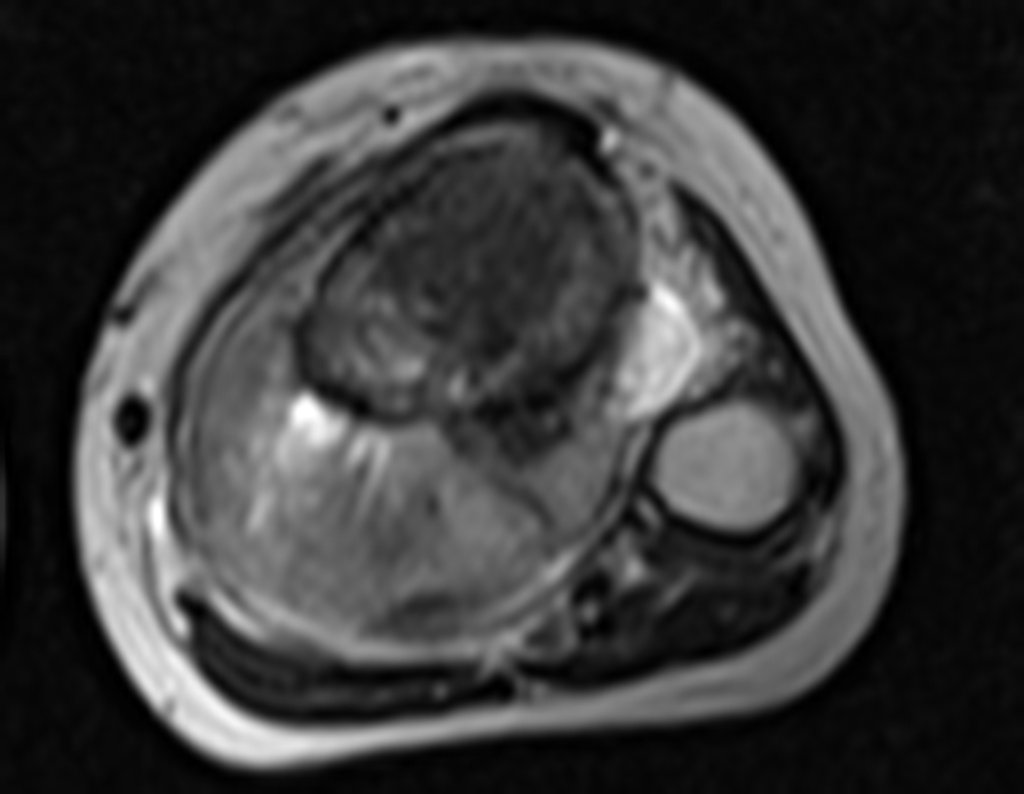

Ingresó en el hospital en mayo y se sometió a una biopsia por punción. El informe anatomopatológico indicó osteosarcoma central convencional localizado, con cultivos negativos. Se le realizó estadificación con TC de tórax, gammagrafía ósea de todo el cuerpo y resonancia magnética del miembro inferior derecho. Se le realizaron tres ciclos de quimioterapia neoadyuvante con Platino y Doxorrubicina, con buena respuesta.